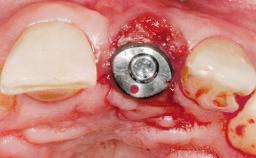

Immediate Placement of an Implant in a Maxillary Right Central Incisor Site

A 30-year-old female patient was referred to the office for the treatment of tooth 11. Her chief concern at the initial visit was to inquire, “Why is my tooth pink?” Upon clinical examination, it was determined that tooth 11 had a previous history of trauma and that the clinical crown had become noticeably pink in color as a result of internal resorption. This diagnosis was confirmed radiographically, indicating a large radiolucency involving the central and distal portions of the clinical crown. It was determined that restoration of this tooth was not possible, and that extraction was indicated. The presence of a mid-line diastema, which the patient wanted to reproduce, directed the treatment plan for tooth replacement utilizing a dental implant.

Placement Protocol Immediate implant placement

Socket Morphology Single-root socket

Socket Integrity Sufficient, with intact bone walls